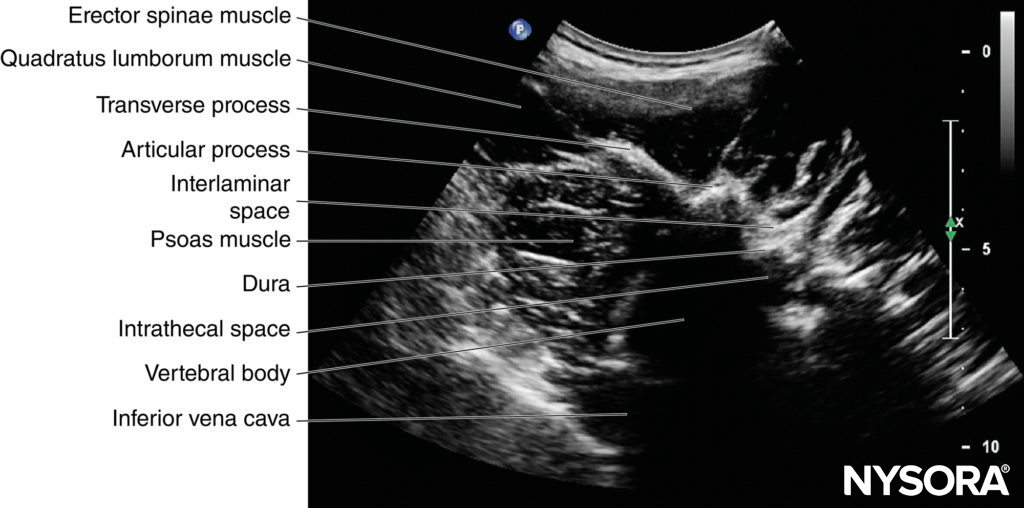

On a typical PMTOS-TP (see Figure 10b), the erector spinae muscle, transverse process, psoas major muscle, quadratus lumborum muscle, and anterolateral surface of the vertebral body are clearly visualized (see Figure 13).

The psoas muscle appears hypoechoic, but multiple areas of hyperechogenicity are also interspersed within the central part of the muscle (see Figure 13). These hyperechoic speckles represent the intramuscular tendon fibers of the psoas muscle and are more pronounced below the level of the iliac crest.

The inferior vena cava (IVC; on the right side) and the aorta (on the left side) are also identified anterior to the vertebral body (see Figure 13) and are useful landmarks to look out for while performing a PMTOS. The lower pole of the kidney, which can extend to the L3–L4 level, is closely related to the anterior surfaces of the quadratus lumborum and psoas muscles and frequently seen as an oval structure that moves synchronously with respiration in the retroperitoneal space (Figure 21). The acoustic shadow of the transverse process obscures the posterior aspect of the psoas muscle during a PMTOS-TP (see Figure 13). Therefore, the lumbar nerve root and lumbar plexus are rarely visualized through the PMTOS-TP scan window. However, the spinal canal, with the dura and the intrathecal space, may be visualized during a PMTOS-TP (see Figure 13) due to the US signal entering the spinal canal through the interlaminar space (see Figure 13). Being able to visualize the neuraxial structures during a lumbar paravertebral scan may be useful in documenting epidural spread after an LPB.

In contrast, during a PMTOS through the lumbar intertransverse space and at the level of the articular process (PMTOS-AP) (see Figure 10c), apart from the erector spinae, psoas, and quadratus lumborum muscles, the intervertebral foramen, articular process, and lumbar nerve root are clearly delineated (see Figure 14). The LPVS is also seen as a hypoechoic space adjacent to the intervertebral foramen (see Figure 14), and the lumbar nerve root can be seen exiting the foramen to enter the paravertebral space (see Figure 14).

After it exits the intervertebral foramen, the lumbar nerve root does not enter the psoas muscle directly opposite the intervertebral foramen from which it emerges (see Figure 14), but takes a steep caudal course (see Figure 14), entering the psoas muscle at the vertebral level below to join the lumbar plexus. The lumbar plexus is seen as a separate hyperechoic structure within a hypoechoic space, the psoas compartment, in the posterior aspect of the psoas muscle (see Figure 14). In a transverse sonogram produced by the shamrock method (see Figure 15), the psoas, erector spinae, and quadratus lumborum muscles are also clearly visualized (see Figures 16, 17, 18 and 19). The anatomical arrangement of the three muscles around the transverse process—that is, the psoas muscle lying anteriorly, the erector spinae muscle lying posteriorly, and the quadratus lumborum muscle lying at the apex (see Figure 16)—produces a sonographic pattern that has been likened to the shape of a “shamrock,” with the muscles representing its three leaves. The lumbar nerve root may also be visualized close to the angle between the vertebral body and the transverse process (see Figure 16) and the lumbar plexus within the posterior aspect of the psoas muscle, typically about 2 cm anterior to the transverse process (see Figures 17 and 18). From this position, if the transducer is gently tilted caudally, the acoustic shadow of the L4 transverse process disappears, and the US beam is now insonated through the intertransverse space and at the level of the articular process of the L4 vertebra, similar to that seen with a PMTOS-AP (see Figure 17). As a result, apart from the psoas, erector spinae, and quadratus lumborum muscles, the intervertebral foramen and lumbar plexus may also be visualized (see Figure 17).